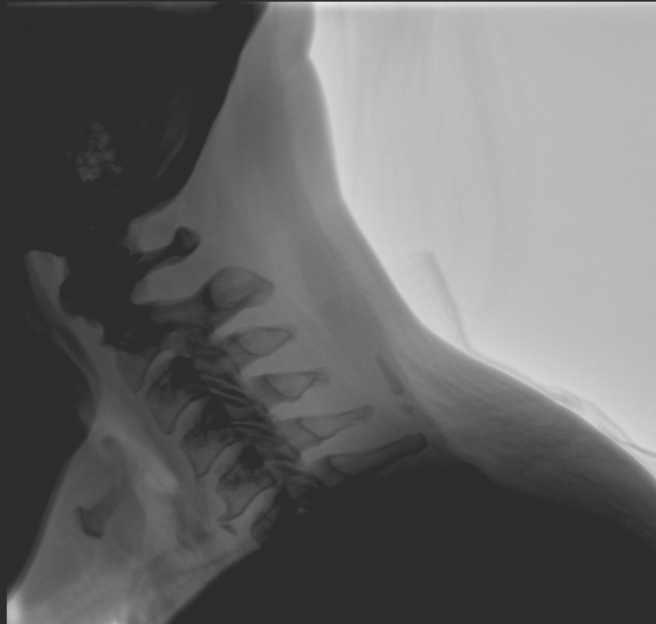

臨床應(yīng)用廣泛,適用于關(guān)節(jié)手術(shù)、創(chuàng)傷手術(shù)、脊柱手術(shù)、疼痛治療等。

●屏幕內(nèi)置DICOM醫(yī)學(xué)曲線,幫助辨認(rèn)細(xì)微組織的密度變化。

●27英寸大尺寸顯示器,更大視野,方便觀察微小結(jié)構(gòu)。

●一屏雙顯,可同時觀察正側(cè)位圖像,便于對比觀察。